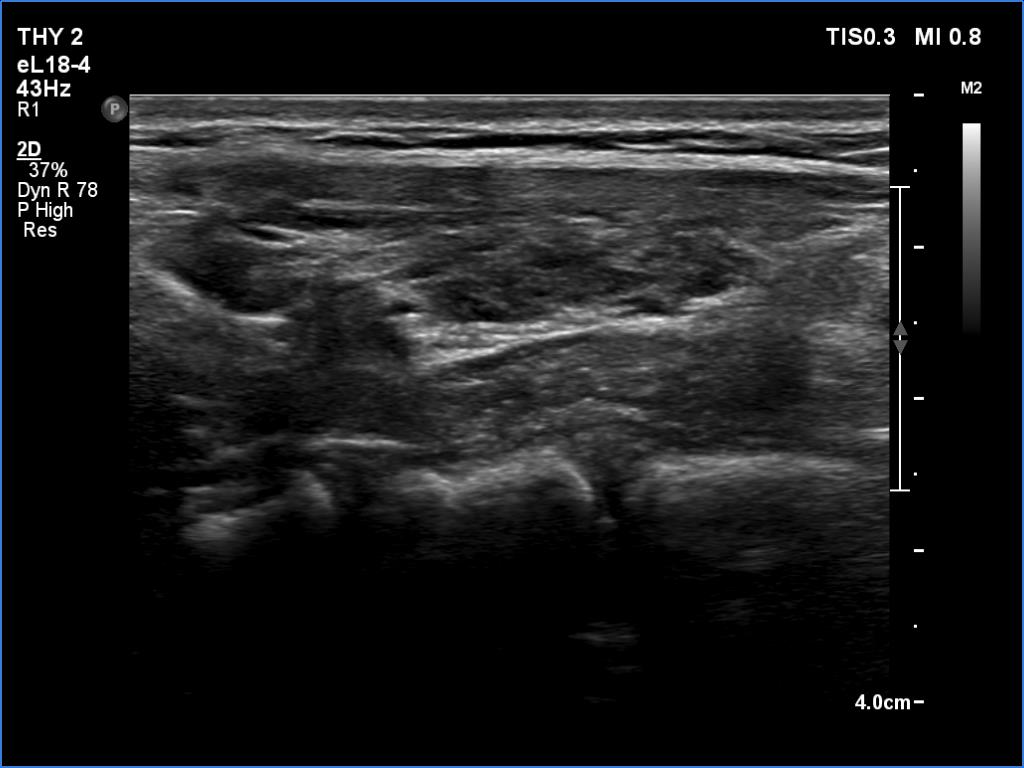

Lymphocytic thyroiditis - case 445 (ultrasonographic picture 4)

Left lobe, longitudinal scan.